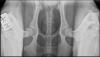

| Beskrivelse | Har du lyst til at blive klogere på HD og hundes risiko for slidgigt, og hvorfor det er en rigtig god ide at bruge PennHIP? Så inviterer region Østjylland til et foredrag med dyrlæge Camilla Juelsgaard Jørgensen.

Camilla er uddannet dyrlæge fra Københavns universitet i 2007 og blev certificeret til at udføre PennHIP i 2016. Camilla bruger en stor del af sin tid på at udrede haltheder og tage røntgenbilleder, bl.a. tager hun ca. 150 HD-billeder til DKK og DJR om året, hvoraf ca. 20 hunde også får taget billeder til PennHIP. Camilla er udover sit virke som dyrlæge selv opdrætter, eksteriørdommer og underviser desuden i genetik på DKK’s opdrætter uddannelse. Camilla vil bl.a. komme ind på følgende emner: •HD, billeder og kvalitet. Bedømmelseskriterier. •Distraktionsindeks, PennHIP mm. •HD-resultaters brug i avlen, HD-indeks mm. Der er 30 pladser (først-til-mølle) |